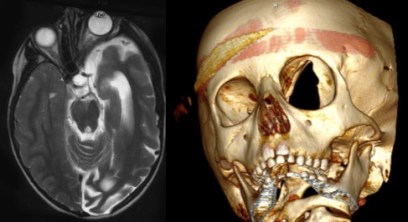

on retrouve en association des lésions tumorales (neurofibrome plexiforme) et dysplasiques (encéphalocèle de la grande aile du sphénoïde) qui constituent le syndrome de François.

la chirurgie est souvent

décevante car le résultat de ces interventions lourdes ne se maintient souvent pas.

en raison de la colonisation du greffon (toît d’orbite) par la maladie, il s’agit ici d’à peu près la seule indication de l’utilisation de ciment acrylique en chirurgie crânais-faciale de l’enfant.